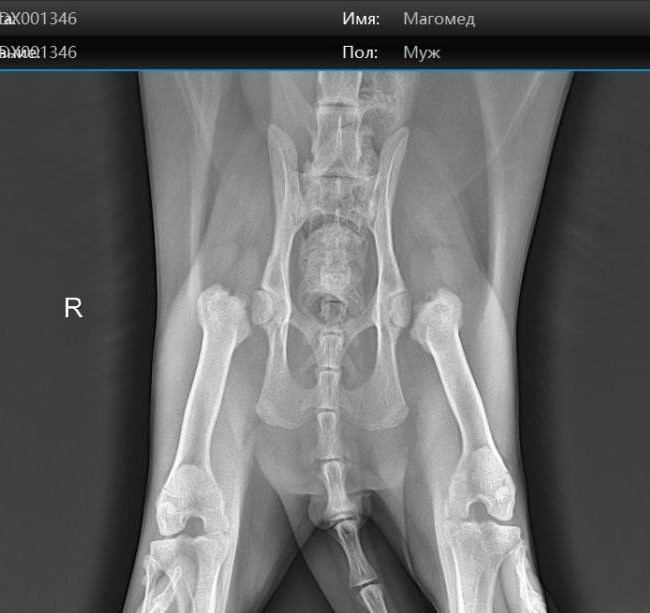

Екатеринбурженка Полина Токарева в ноябре 2019 года купила себе котенка породы мейн-кун в питомнике Bayt-ares на Уралмаше. Впоследствии у малыша, которого назвали Магомедом, проявились серьезные проблемы со здоровьем: у него обнаружили диафизарную дисплазию тазобедренного сустава и гипертрофическую кардиомиопатию (болезнь сердца).

Диафизарная дисплазия и гипертрофическая кардиомиопатия — заболевания, которые часто встречаются у котов породы мейн-кун. Дисплазия возникает из-за того, что котята слишком быстро растут. Передается болезнь, в ходе которой разрушаются суставы, от родителей. Как и кардиомиопатия, при которой стенки сердца увеличиваются и не могут качать кровь.